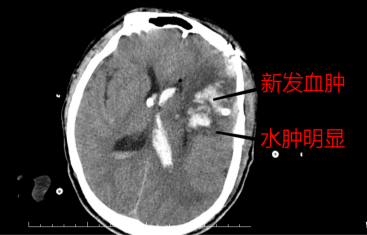

复查头部ct示:术区新发出血(王先生本身血管质量差导致),且脑水肿较之

图片尺寸367x235